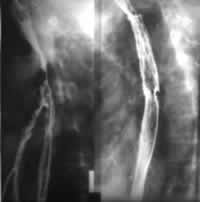

1.食管鋇餐造影根據鋇餐造影的影像特點,食管狹窄可分兩型。

(1)長段型:狹窄發生於食管中下段,長約數厘米。狹窄邊緣欠光滑,狹窄段以上食管擴張,鋇劑下行緩慢,可見逆蠕動。本型臨床症狀出現較早,與反流性食管炎相似,X線難以鑑別。

(2)短段型:常發生於食管中、下段交界處,狹窄段長約數毫米至1cm,邊緣光滑,黏膜規則。狹窄段以上食管輕度擴張,鋇劑下行尚可,狹窄遠段食管形態正常。有時於狹窄之上易發生異物或食物塊存留。狹窄段不能擴張。本病常合併吸入性肺炎,鋇餐檢查時要常規胸透。